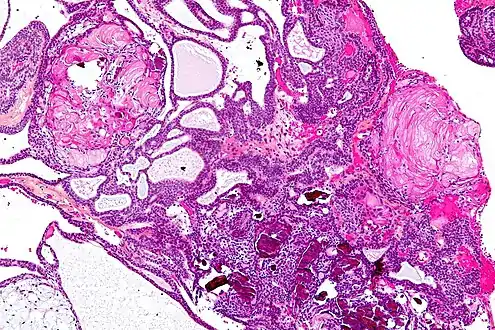

On macroscopic examination, craniopharyngiomas are cystic or partially cystic with solid areas. On light microscopy, the cysts are seen to be lined by stratified squamous epithelium. Keratin pearls may also be seen. The cysts are usually filled with a yellow, viscous fluid rich in cholesterol crystals. Of a long list of possible symptoms, the most common presentations include headaches, growth failure, and bitemporal hemianopsia.

Micrograph showing the characteristic features of an adamantinomatous craniopharyngioma - cystic spaces, calcifications, and "wet" keratin, HPS stain

Micrograph showing a papillary craniopharyngioma, HPS stain